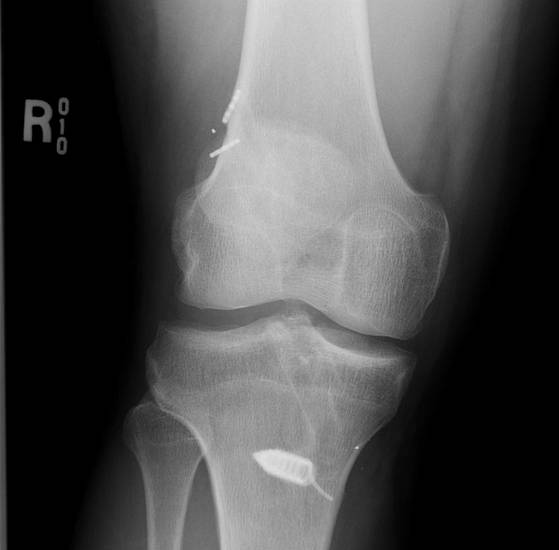

Patient previous failed hamstring ACL likely from posterior tibial tunnel. Revision ACL with contralateral hamstring with new tunnel drilled anterior in tibia. Tibial tunnel now too anterior and revison also failed.

ACL 8 years ago, traumatic rupture. Femoral tunnel too vertical from transtibial drilling. New femoral tunnel at 10 o'clock position completely separate from old tunnel by using anteromedial portal. Tibial tunnel exits at same point, but entrance more medial on tibia and guide set at 65o to ensure different tunnel. Tibialis posterior allograft used - 10 mm in diameter over endobutton.